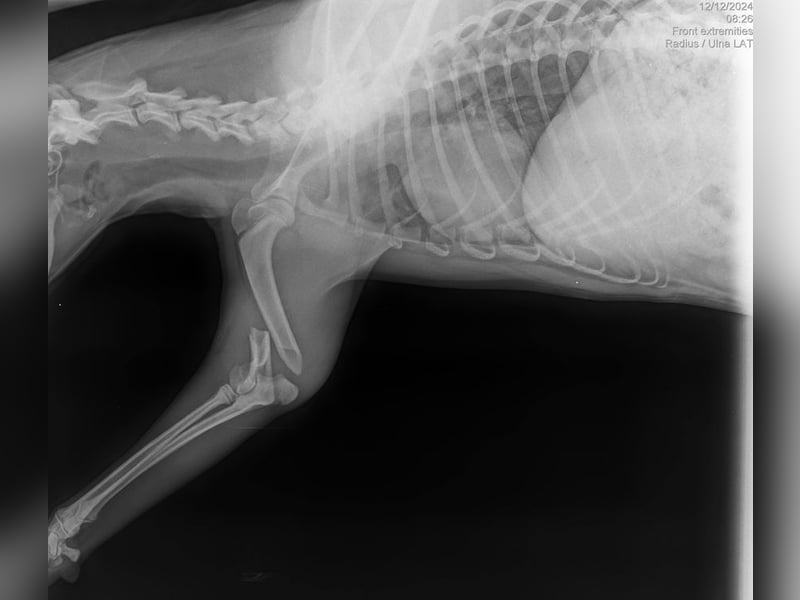

Bemerkungen: Olivia kam mit einem gebrochenen Vorderbein im Tierheim an.

Olivia stammt aus den Straßen eines Nachbardorfes. Sie wurde dort mit einem gebrochenen Vorderbein gefunden und im Tierheim abgegeben.

Der Bruch musste allerdings schon älter sein, denn im oberen Teil des Beines hatte sich bereits eine Osteomyelitis (Knochenmarksentzündung) entwickelt. Das Bein wurde operiert, blieb aber kürzer. Olivia nutzt es zur Begrüßung von Menschen, indem sie es ständig ausstreckt und beim Essen gelegentlich Gewicht darauf verlagert. Sie läuft und spielt aber hauptsächlich auf drei Beinen.

Die Tierärzte entschieden, das Bein zu behalten, da es noch eine gewisse Funktion hat.

Bemerkungen: Olivia kam mit einem gebrochenen Vorderbein im Tierheim an.

Olivia stammt aus den Straßen eines Nachbardorfes. Sie wurde dort mit einem gebrochenen Vorderbein gefunden und im Tierheim abgegeben.

Der Bruch musste allerdings schon älter sein, denn im oberen Teil des Beines hatte sich bereits eine Osteomyelitis (Knochenmarksentzündung) entwickelt. Das Bein wurde operiert, blieb aber kürzer. Olivia nutzt es zur Begrüßung von Menschen, indem sie es ständig ausstreckt und beim Essen gelegentlich Gewicht darauf verlagert. Sie läuft und spielt aber hauptsächlich auf drei Beinen.

Die Tierärzte entschieden, das Bein zu behalten, da es noch eine gewisse Funktion hat.